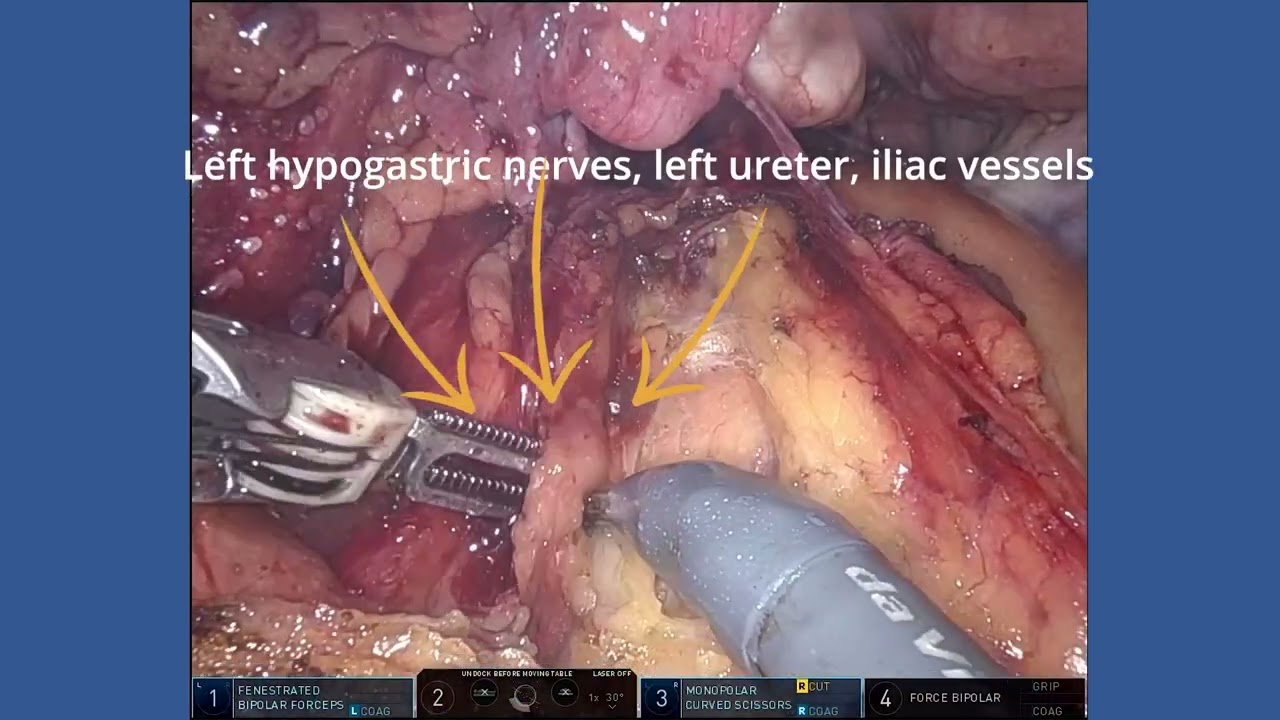

#295 AUTONOMIC NERVE PRESERVING ROBOTIC RECTAL SURGERY- ”RADICALITY WITH FUNCTIONALTY” Dr. K Agrawal

KS Awards, Robotics, Surgeon ';